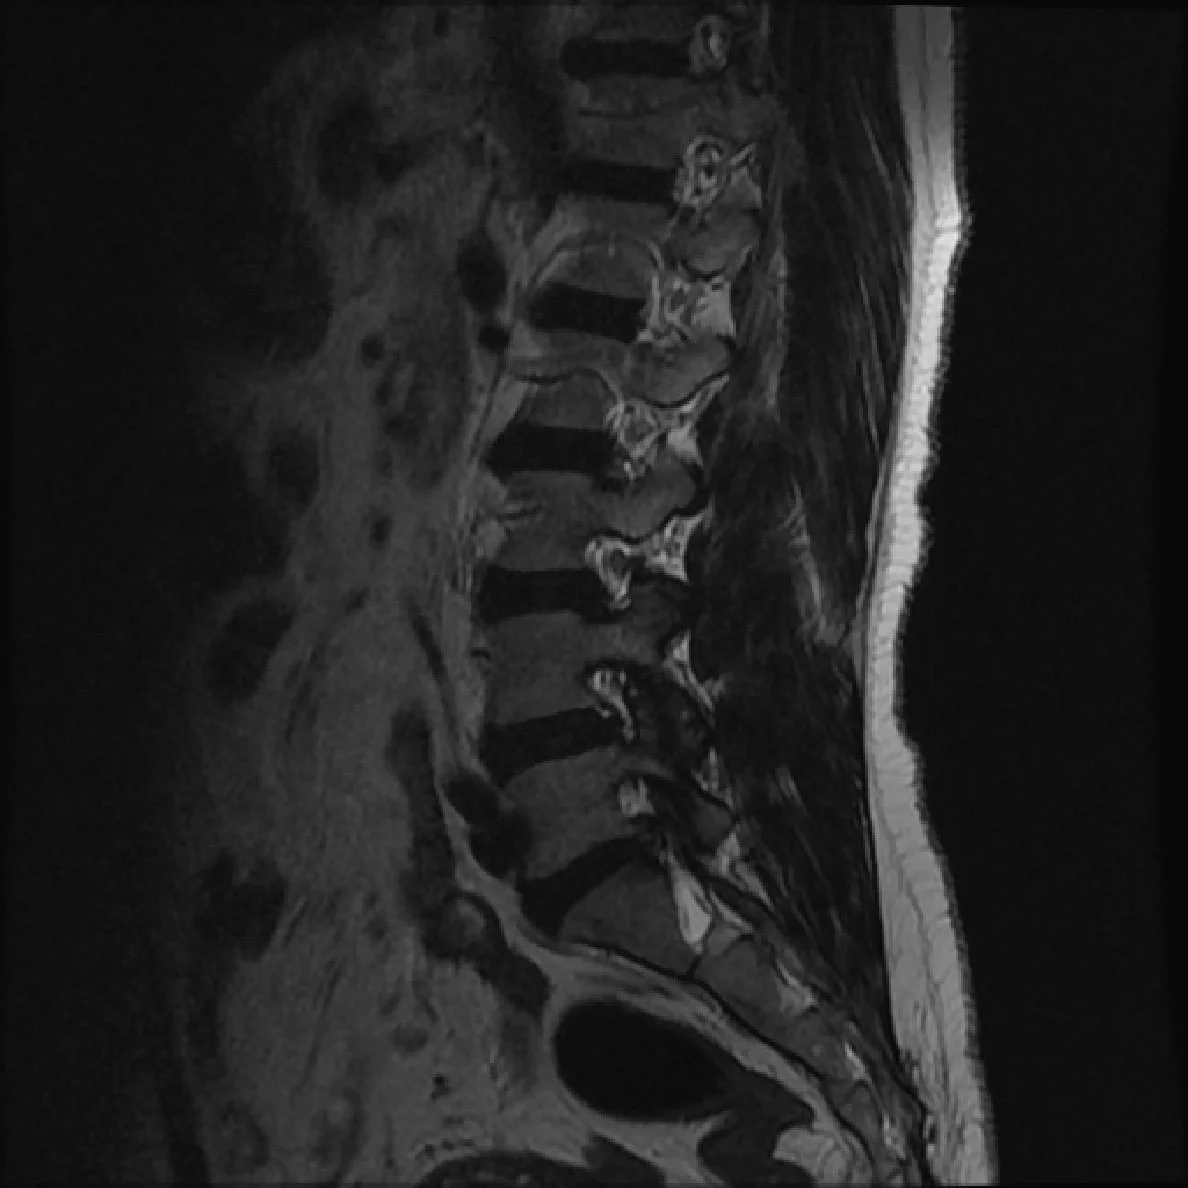

• For all spine masses need to determine

• Intramedullary vs. Intradural Extramedullary vs. Extradural

Intramedullary

Intra-dural Extra-medullary

• Astrocytoma & Ependymoma

• T1-hypo

• T2-hyper

• Variable enhancement

Extra-dural